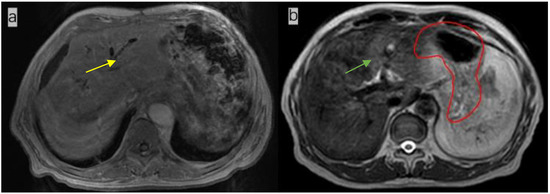

Figure 2.

Comparison of images of the whole stomach on the same plane after the 1st, 5th, 10th, and 15th fractions, showing the radiation oncologist’s delineation (red line) and the delineation obtained with AI (orange line). The dice similarity coefficient (DSC) of the three-dimensional stomach images indicated by these four outlines are 0.8311 (a), 0.9185 (b), 0.9193 (c), and 0.9427 (d), respectively.